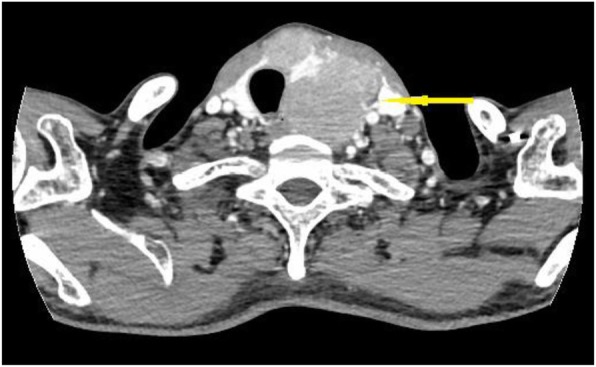

A 47-year-old male patient suffering from mild abdominal pain for 2 months was admitted to our hospital in February 2018. He was diagnosed with “acute pancreatitis” first before transferring to our department. The ultrasound (US) and computed tomography (CT) scan of the abdomen revealed a pancreatic space-occupying lesion and pancreatic duct dilatation (Fig. 1). The serum amylase and lipase levels were slightly elevated (231 and 546 U/L, respectively; normal range: 25–125 and 13–60 IU/L, respectively). the preoperative serum CA 19–9 level was 34.82 U/ml. Then, the patient underwent exploratory laparotomy. Intraoperative examination identified a hard mass in the body (approximately 4.0 cm × 3.0 cm) and tail of the pancreas, varicose veins around the spleen, a mass in the diaphragm (1.5 cm diameter), and three light masses on the surface of the liver. One mass was taken for pathological examination of the intraoperative rapid frozen section, and the result showed adenocarcinoma in the mass. The patient underwent radical distal pancreatectomy, splenectomy, diaphragm, and liver mass resection. The patient manifested with obstructive jaundice after surgery and gradually increased level of bilirubin. The total bilirubin increased from 65.4 μmol/L to 105.6 μmol/L and then to 140.1 μmol/L, and the direct bilirubin increased from 53.8 μmol/L to 81.0 μmol/L and then to 118.1 μmol/L. Subsequently, the patient underwent cholangiojejunostomy, and the pathological report revealed resected masses from the pancreas, liver, and diaphragm, indicating PTC metastases (Fig. 2). Immunohistochemical studies showed positive stanning of TG(+), PAX-8(+), TTF-1(+), CK19(+), HBME-1(+), Galectin-3(+), P53(+), WT(+), DPC4(+), CA19–9(luminal surface+), MUC1(+), with negative staining of MUC5AC(−), MUC6(−), MUC2(−). Then, the patient had a thyroid US, which showed multiple hypoechoic masses in the left thyroid gland and an endoscopic US-guided fine needle aspiration (FNA) biopsy of the thyroid mass. Pathology also revealed papillary cancer. After the patient had recovered in the pancreatic department, he was transferred to the thyroid department. A CT scan was taken, and the result showed large masses in the isthmus and left lobes of the thyroid, multiple enlarged lymph nodes, and multiple masses in the bilateral parotid and submandibular gland (Figs.3 and 4). Then, the patient received an FNA biopsy of the parotid and submandibular mass, and the result showed PTC metastases. Immunohistochemical studies showed TTF-1(+), TG (−), CK19(+), HBME-1(+), Galectin-3(+), Villin(−), CDX-2(−). In July 2018, he received complete thyroidectomy, cervical lymphadenectomy, bilateral parotidectomy, bilateral submandibular gland and left recurrent laryngeal nerve resection. Intraoperative examination showed a huge irregular mass (approximately 10.0 cm × 7.0 cm × 5.0 cm) in the left and isthmus of the thyroid gland with calcification. The mass invaded the left recurrent laryngeal nerve and adhered to the surface of the trachea, and enlarged lymph nodes (3.5 and 2.5 cm in diameter) were found in the bilateral parotid. Multiple small enlarged lymph nodes (diameter ranging from 0.3 cm to 1.5 cm) were also noted in the bilateral submandibular gland. Intraoperative rapid frozen biopsy showed papillary cancer. The final histopathology revealed bilateral thyroid and isthmic papillary carcinoma and cervical lymph node metastasis, and papillary cancer in the left parotid and bilateral submandibular glands but not in the right parotid gland. Immunohistochemical studies showed CK19(+), HBME-1(+), Galectin-3(+), TG (partial+), TTF-1(+), P53(partial+), NapsinA (−), PD-L1(+, approximately 10%). The gene test showed activated mutation detected in the exon 15 of the BRAF gene (V600E) and the promoter 228 of TERT. After surgery, the patient was given radioiodine-131 therapy. He recovered well and was discharged from the hospital with oral Euthyrox therapy. The patient still survives at present.

Fig. 4.

CT scan showed multiple masses in the bilateral parotid and submandibular gland